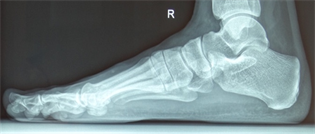

Figure 18. Patient Nr. 4. Bilateral moderate hallux valgus.

Figure 19. Patient Nr. 4. Side view left foot.

Figure 20. Patient Nr. 4. Side view right foot.

Figure 21. Patient Nr. 4. 5 years after bilateral correction. Outpatient. Immediate full weight bearing.

Figure 22. Patient Nr. 4. Side view of the left foot shows the plantarization of 2 mm.

Figure 23. Patient Nr. 4. Side view of the right foot shows the plantarization of 2 mm.